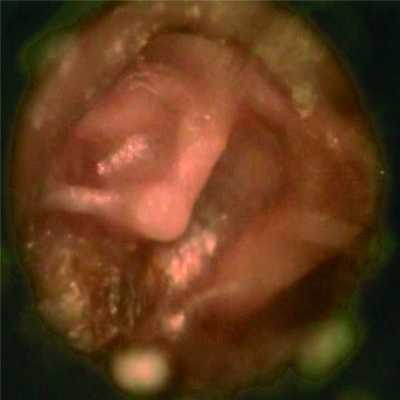

В 11 (47,8%) случаях/15 (42,9%) ушей аттиковых и смешанных ретракций у пациентов дно РК не прослеживалось, при этом отмечалось разрушение латеральной стенки аттика у 5 (21,8%) человек/6 (17,2%) ушей. Отомикроскопическая картина соответствовала атрофичной, коллаптированной барабанной перепонке с фиксацией ее на медиальной стенке барабанной полости, с мирингоинкудостапедопексией (рис. 3 на цв. вклейке), Рисунок 3. Смешанная ретракция барабанной перепонки IV типа. Коллапс барабанной полости. Мирингоинкудостапедопексия (стадия адгезии). в 2 (5,7%) случаях — с мобильным ретракционным карманом.